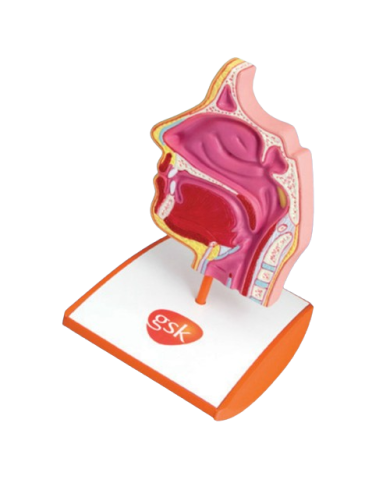

Modello anatomico PER FORNITURE CASE FARMACEUTICHE

Modello anatomico PER FORNITURE CASE FARMACEUTICHE

Modello anatomico PER FORNITURE CASE FARMACEUTICHE

Modello anatomico PER FORNITURE CASE FARMACEUTICHE

Modello anatomico PER FORNITURE CASE FARMACEUTICHE

Modello anatomico PER FORNITURE CASE FARMACEUTICHE

Modello anatomico PER FORNITURE CASE FARMACEUTICHE

Modello anatomico PER FORNITURE CASE FARMACEUTICHE

Modello anatomico PER FORNITURE CASE FARMACEUTICHE

Modello anatomico PER FORNITURE CASE FARMACEUTICHE

Modello anatomico PER FORNITURE CASE FARMACEUTICHE

Modello anatomico PER FORNITURE CASE FARMACEUTICHE

Modello anatomico PER FORNITURE CASE FARMACEUTICHE

Modello anatomico PER FORNITURE CASE FARMACEUTICHE

Modello anatomico PER FORNITURE CASE FARMACEUTICHE

Modello anatomico PER FORNITURE CASE FARMACEUTICHE

Modello anatomico PER FORNITURE CASE FARMACEUTICHE

Modello anatomico PER FORNITURE CASE FARMACEUTICHE

Modello anatomico PER FORNITURE CASE FARMACEUTICHE

Modello anatomico PER FORNITURE CASE FARMACEUTICHE

Modello anatomico PER FORNITURE CASE FARMACEUTICHE

Modello anatomico PER FORNITURE CASE FARMACEUTICHE